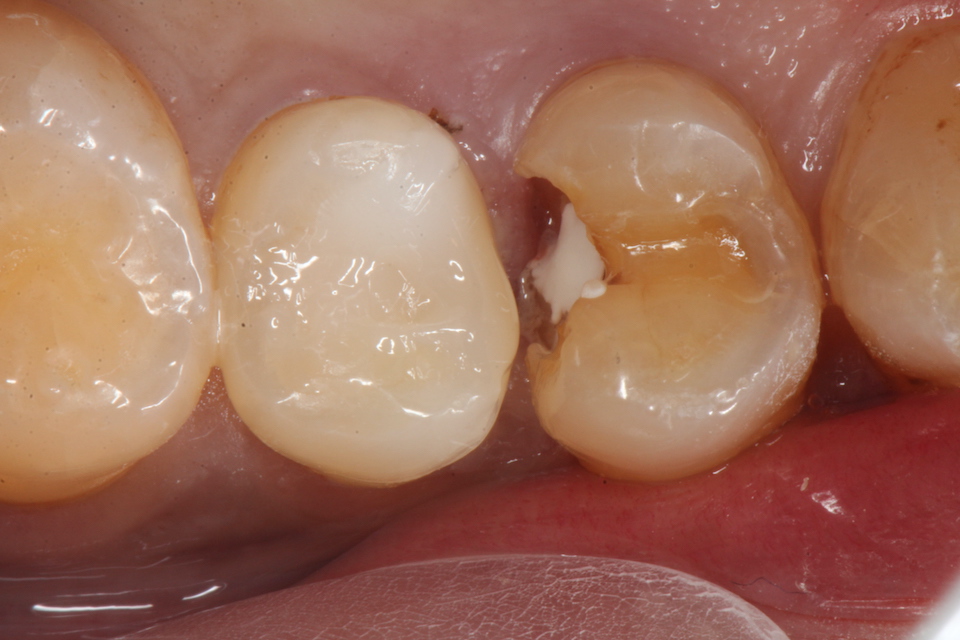

下顎7番の頬側歯茎部カリエスの原因 2025.06.04